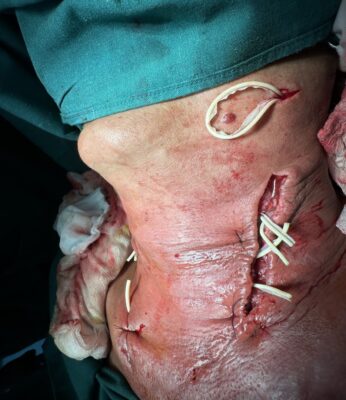

Những ngày tiếp theo sau khi dùng kháng sinh liều cao, phối hợp kháng sinh, vùng viêm lan dần xuống vùng cổ trước và hõm ức, nguy cơ chèn ép đường thở và dịch mủ lan xuống trung thất gây nguy hiểm đến tính mạng bệnh nhân. Sau khi có kết quả chụp MRI, siêu âm vùng cổ và các xét nghiệm cho phép rạch tháo mủ, Khoa Răng Hàm mặt đã tiến hành hội chẩn Bệnh viện và tham khảo ý kiến chuyên gia của Bệnh viện Đà Nẵng thống nhất chẩn đoán viêm tấy lan tỏa vùng dưới hàm, cổ trước giai đoạn hóa dịch hoàn toàn do viêm tuyến nước bọt mang tai, dưới hàm trái phải phẫu thuật cấp cứu dẫn lưu dịch mủ ra ngoài tránh các biến chứng nguy hiểm. Các bác sĩ của Khoa phối hợp với khoa Ngoại chung, khoa Phẫu thuật gây mê hồi sức đã phẫu thuật cấp cứu thành công. Bệnh nhân được phẫu thuật rạch rạch rộng vùng cổ 2 bên, tháo mủ, dẫn lưu ra khoảng 80ml dịch mủ trắng, thay băng bơm rửa 2 lần/ngày, lấy dịch mũ cấy khuẩn và làm kháng sinh đồ. Sau khi có kết quả cấy khuẩn, bênh nhân được dùng thuốc theo kháng sinh đồ, tình trạng viêm lan tỏa được khống chế, lượng dịch mủ giảm, toàn trạng bệnh nhân tốt lên, số lượng bạch cầu giảm dần.

Hình 4. Ảnh chụp tổn thương sau mổ

Phương pháp điều trị phẫu thuật được thực hiện dưới gây mê, với đường rạch dài từ dưới hàm đến cán xương ức 2 bên, lấy bỏ các mô hoại tử, mở rộng đến các ổ viêm loại bỏ triệt để dịch mủ, sau đó là dẫn lưu, băng ép. Sau phẫu thuật cần phải thực hiện thay băng, bơm rửa 2 lần/ngày để loại bỏ tất cả các mô hoại tử và ngăn chặn quá trình hoại tử mô lan rộng. Phẫu thuật là một phần quan trọng trong việc kiểm soát các dạng viêm mô tế bào nghiêm trọng giảm thiểu nguy cơ chèn ép đường thở hoặc lan xuống trung thất [10]. Dịch mủ được lấy và gửi làm kháng sinh đồ.